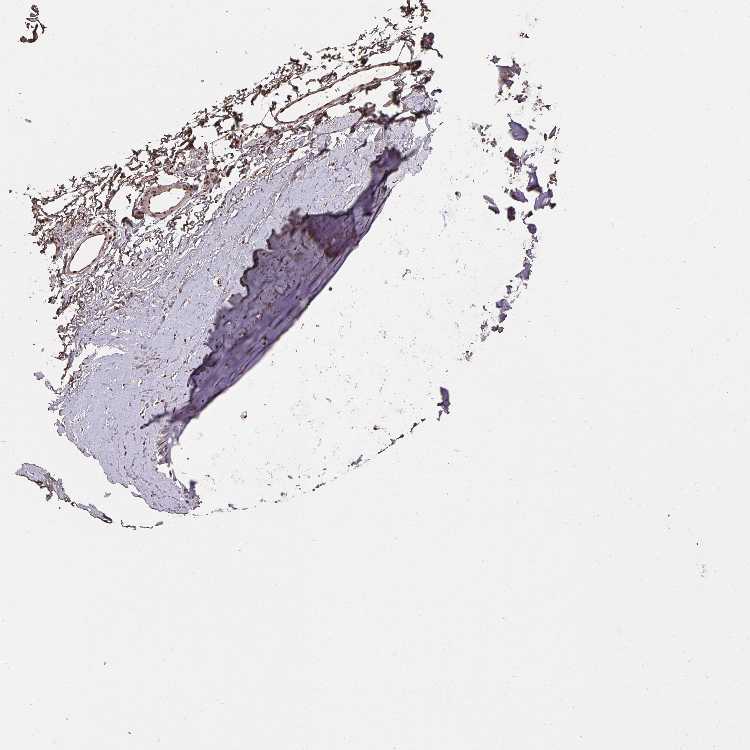

SOFT TISSUE 1 - Antibody stainingi

Antibody staining in the annotated cell types in the current human tissue is reported as not detected, low, medium, or high, based on conventional immunohistochemistry profiling in selected tissues. This score is based on the combination of the staining intensity and fraction of stained cells.

Each image is clickable and will lead to virtual microscopy that enables deeper exploration of all samples and also displays staining intensity scores, fraction scores and subcellular localization as well as patient and tissue information for each sample.

Antibody HPA061463

Chondrocytes Medium

Fibroblasts Medium

Peripheral nerve Medium

SOFT TISSUE 2 - Antibody stainingi

Fibroblasts High